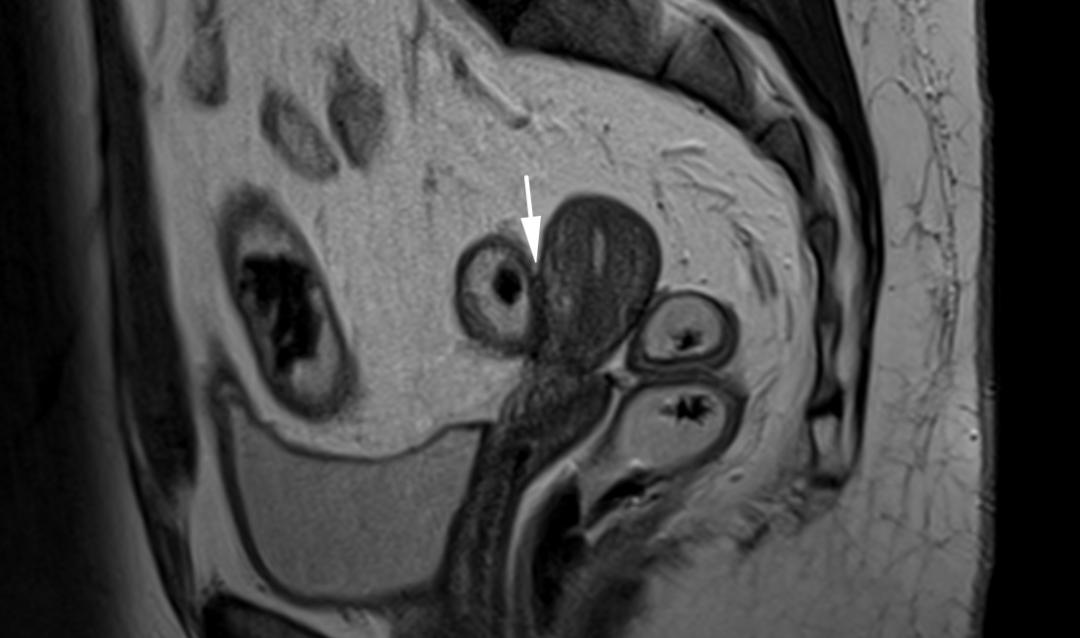

CASE 6

子宫内膜异位至右侧卵巢,T2WI 矢状位呈类圆形高信号,注意的是同时异位至道格拉斯窝及宫颈后区,T2WI 矢状位显示病灶呈低信号,中间夹杂更高信号结节,T1WI 轴位显示病灶多发高信号结节(提示多发出血点)